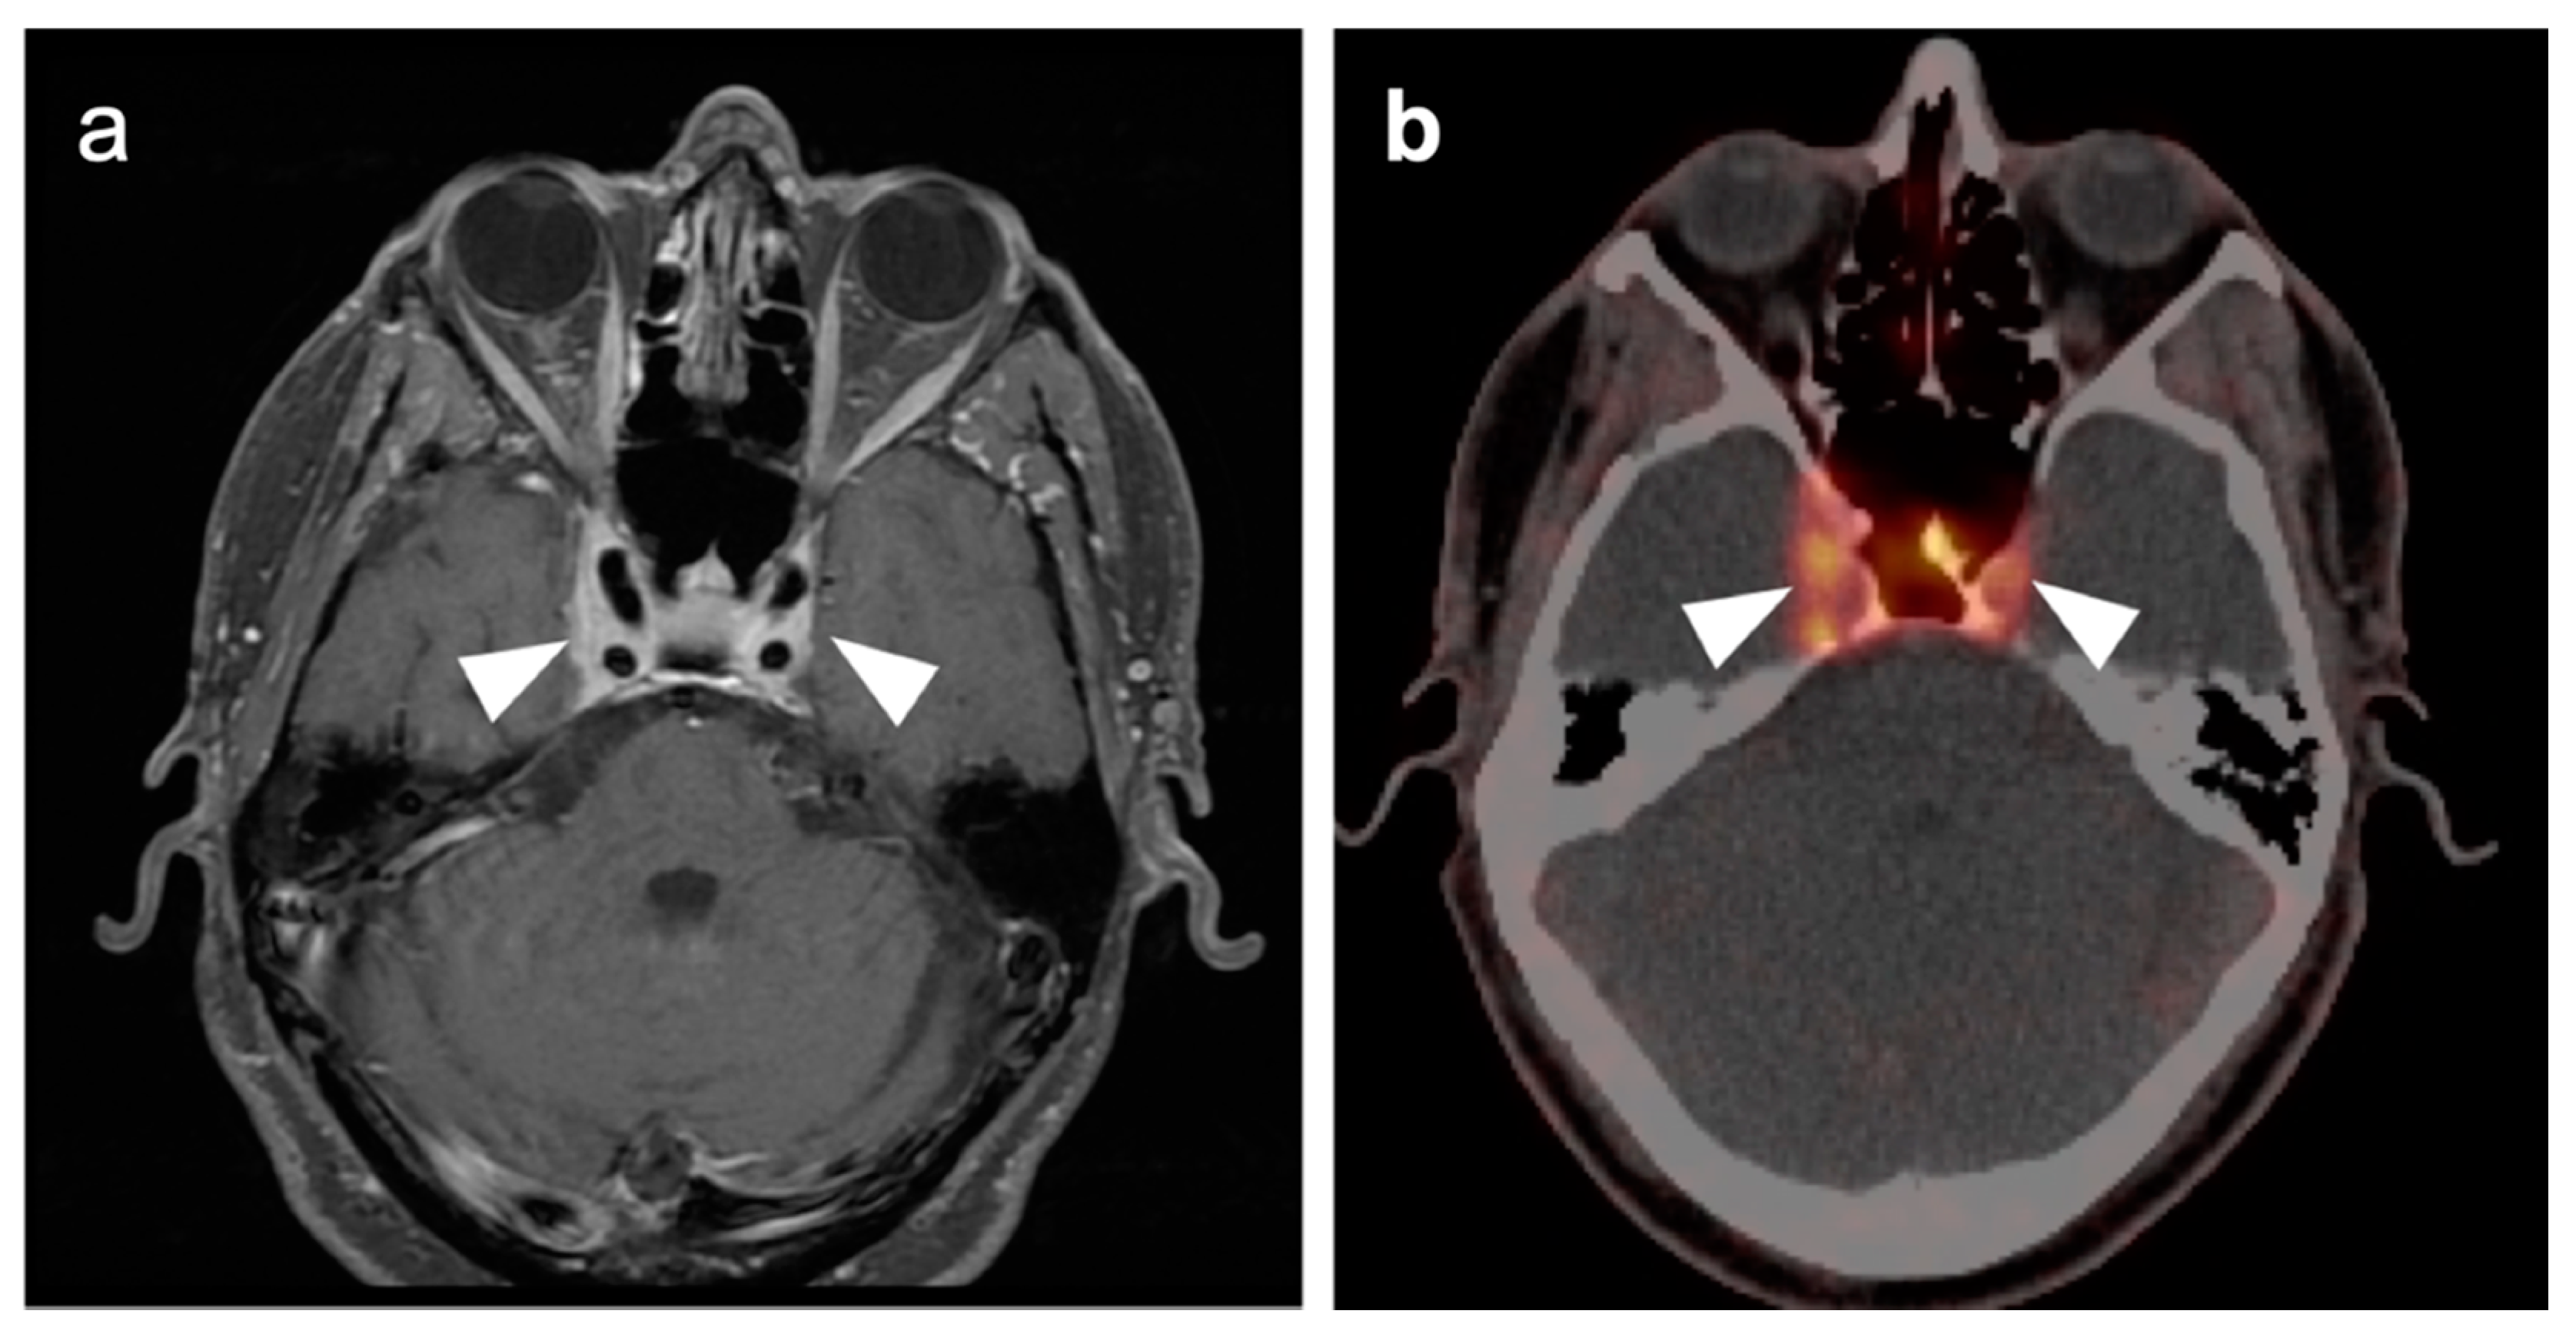

2.3. Nasopharyngeal Carcinoma

2.4. Sinonasal Tumors